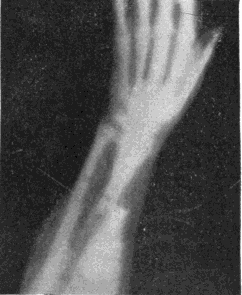

Fig. 2.—Broken Arm, Overlapping.

(Due to defective setting.)